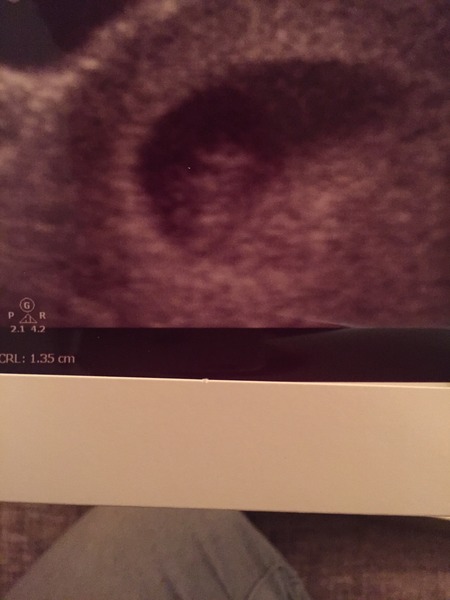

Eek we saw a blob with a heartbeat! I have never been so happy to see a non-descript blob in my life Grin

Yay keep! A beautiful blob it is too Smile

Nice one Keep. Now get ready for the really freaky bit where that blob turns into an identifiable baby in just a few weeks Smile